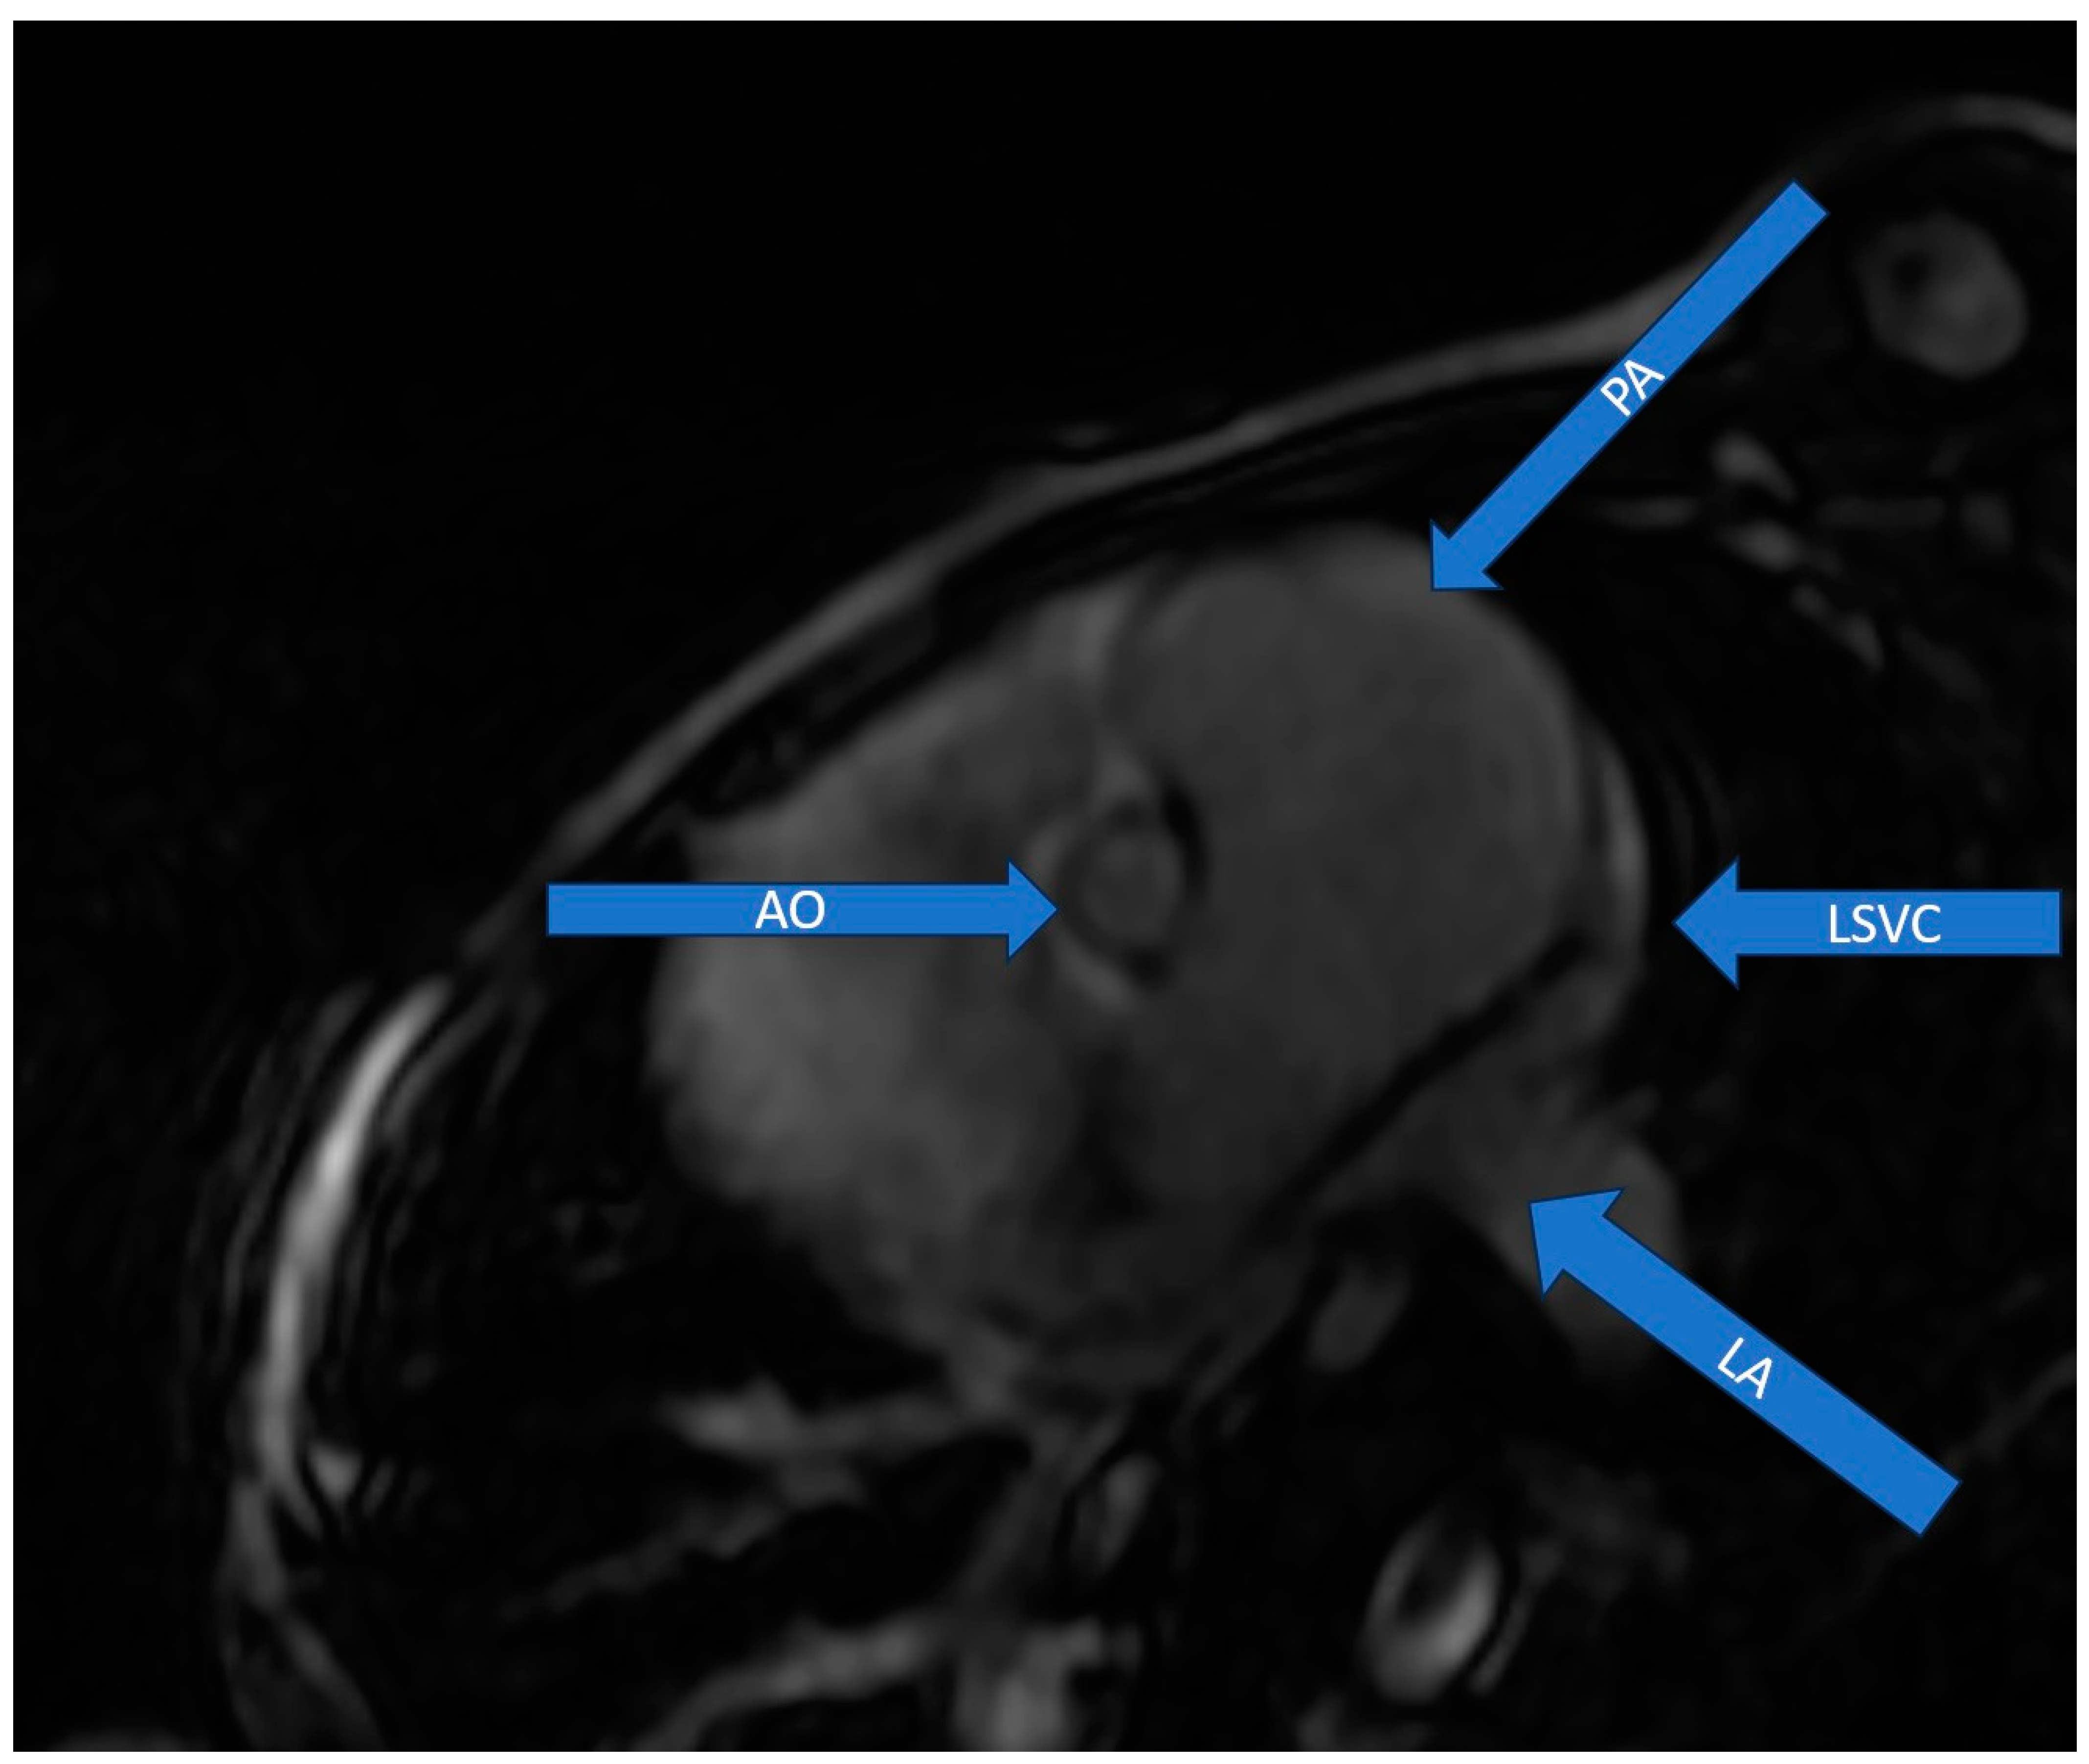

2.2. Diagnostic Assessment